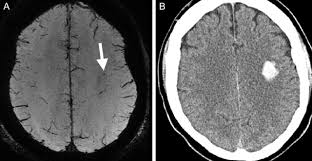

ent with an intracerebral hemorrhage will sometimes be admitted to the internal medicine service when there is a lack of surgical indication, and/or additional medical problems. As a result, internists need to be familiar with how to manage this condition with the support of neurologists and neurosurgeons. Focusing on the medical management of patients, several categories of therapy have been studied: blood pressure control, coagulation, hyperglycemia and others.

Balancing blood pressure in a patient with ICH attempts to control intracerebral pressure (ICP) and cerebral perfusion pressure (CPP). Hypertension is associated with larger volume ICH and hence functional impairment, and as a result its suspected that lowering blood pressure may improve outcomes. The trade-off being that lowering the blood pressure too much would impair cerebral perfusion and would cause hypoxia in susceptible brain tissue. A study looking at CPP in patients treated with anti-hypertensives in ICH found that dropping systemic BP didnt alter CPP. Though the patients in the study were not significantly hypertensive to begin with. The current guidelines recommend targeting a sysBP of less than 160/90 in patients who do not have evidence of high ICP. If high ICP is presents an ICP monitor may be considered to guide CPP.

Hyperglycemia is associated with worse outcomes in patients with ischemic/hemorrhagic stroke. A general target of less than 10mmol is thought to be appropriate according to current guidelines. Patients with ICH associated with anti-coagulant medications are more likely to have worse outcomes. Treatment with activate FVII has been studied and was associated with less hematoma expansion, and decreased mortality in soem studies. Factor aVII does place patients at increased risk for clotting and should not be given lightly. At certain hospitals, only neurosurgeons and transfusionists can approve the use of this medication. Other less helpful treatments that have been pursued include corticosteroids, which were actually associated with an increased rate of infection.